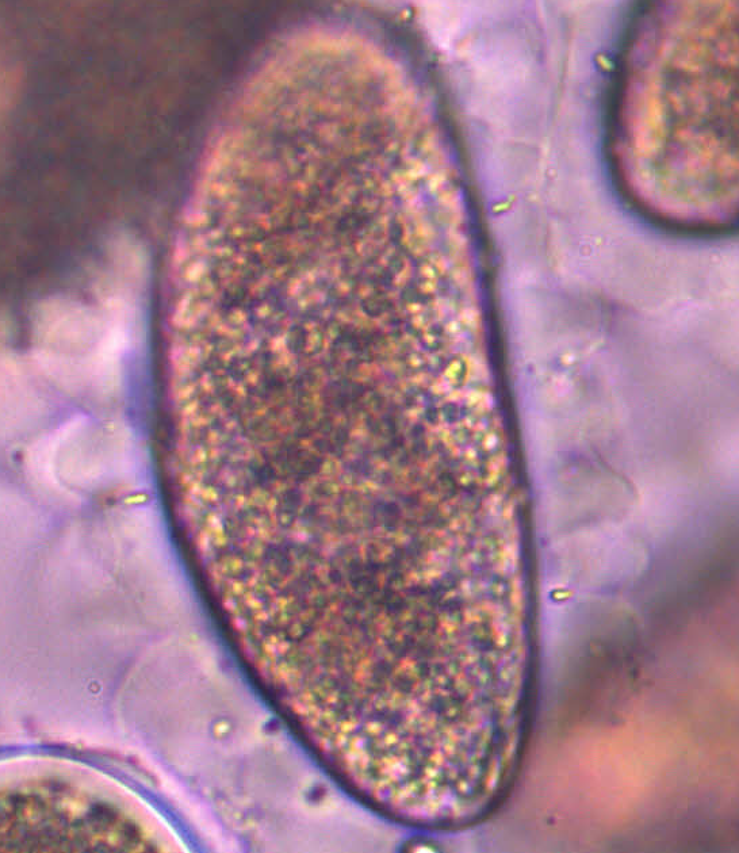

Schistosoma mansoni - Przywra żylna - Jajo